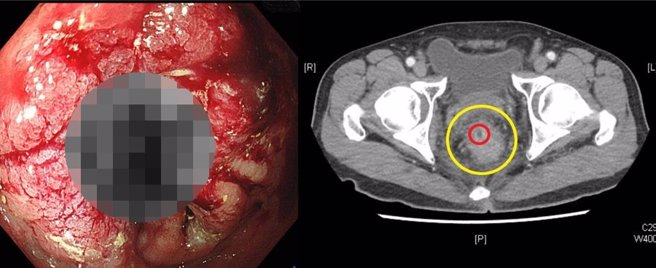

藉由大肠镜影像可看出直肠癌造成出血,电脑断层(右图) 黄圈处为肠道原始大小,因恶性肿瘤阻塞造成肠道管径变小至红圈处,导致排便困难。.(土城医院提供)

60岁萧姓男子血便长达1年,起先以为是痔疮出血,便自行在药局购买药膏涂抹,近期因出血量增加且排便困难,症状没有减缓,不得已只好前来新北市立土城医院就医。医师在诊间初步以肛门指诊,即发现直肠肿瘤,随后安排电脑断层与核磁共振影像及大肠镜切片检查,诊断为第三期低位直肠癌。